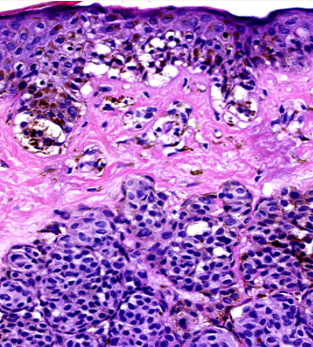

Spitz 痣(斯皮茨痣):主要见于儿童和青少年,常表现为粉红色、红色或棕黑色的丘疹或结节(图6),表面光滑,生长较快,容易被误认为黑色素瘤。但 Spitz 痣本质上是良性的,多数情况下无需特殊处理,部分与黑色素瘤相关,也将作专题介绍。

Spitz 痣(斯皮茨痣)